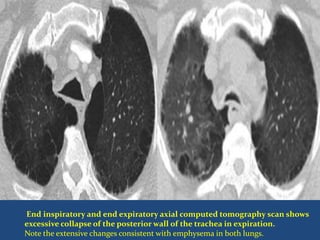

End inspiratory and end expiratory axial computed tomography scan shows

excessive collapse of the posterior wall of the trachea in expiration.

Note the extensive changes consistent with emphysema in both lungs.

• 35.

End inspiratory andend expiratory axial computed tomography scan shows excessive collapse of the posterior wall of the trachea in expiration. Note the extensive changes consistent with emphysema in both lungs.